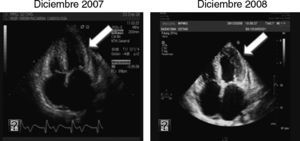

En diciembre de 2008 se repitió ecocardiografía, que mostró en esta ocasión; estenosis aórtica severa con un gradiente transvalvular mayor de 90mmHg (aumento de más de 50mmHg en tan solo un año de evolución del desajuste del HTP 2.°) (figs. 1 y 2), estenosis mitral moderada, dilatación de ambas aurículas e hipertensión pulmonar severa. Dichos hallazgos, motivaron la decisión de sustitución quirúrgica de la válvula aórtica por una válvula protésica.